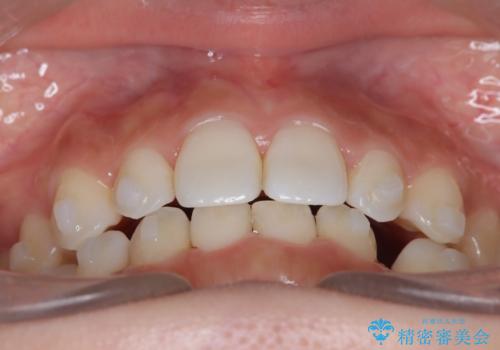

- 空隙歯列を主訴に来院された患者様です。

ばらけている空隙を一箇所に集めながら咬合や正中を改善して最後に補綴治療を行なっています。

右上の臼歯クロスバイトは骨格生のため、そのままにしています。